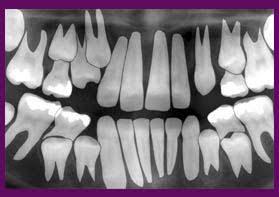

Serial extraction treatment in chennai Serial extr...